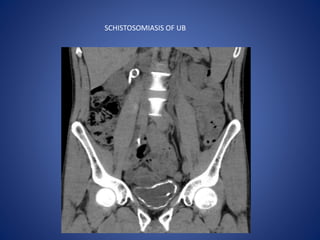

SCHISTOSOMIASIS OF UB